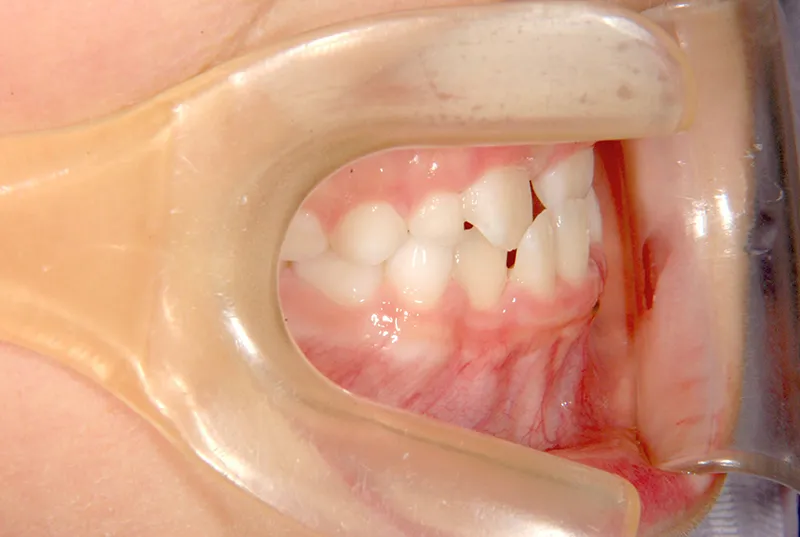

初診時年齢 小学校1年生 (男性) 主訴 すきっ歯・ガタガタ・受け口

診断名 叢生・反対咬合・空隙歯列 装置名

特徴 ゆがんで生えている

状態 永久歯が生える隙間がない(叢生)

受け口(下顎前突/反対咬合)

すきっ歯(空隙歯列)

上の前歯が下の前歯より後ろに入って、受け口になっています。

下の歯は永久歯の生えるスペースがないので、オリジナル矯正装置で受け口を治して、永久歯の生えるスペースを作りました。